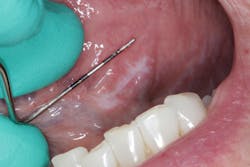

Patient: 62-year-old female

- 9 mm x 3 mm white leukoplakic patch of tissue on left ventral surface of the tongue

- Patient was unaware of its presence

- Not tender to palpation and could not be scraped off

- Noncontributory health history (patient was taking vitamin D supplements)